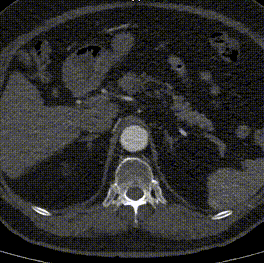

案例三(梯形瘤颈):3年前肾结石,在治疗复查过程中发现腹主动脉瘤。

案例四(梯形瘤颈):因下肢髋部疼痛行腰椎检查时发现腹主动脉瘤,进一步CTA认证确诊为腹主动脉瘤。

案例五:查体发现腹主动脉,行CTA确认腹主动脉瘤伴血栓形成。